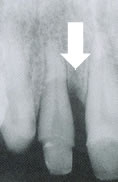

症例6. 再生療法-EPPT-

| 右上2番 | 遠心の垂直性骨欠損 |

![]() |

| 術後 | ほとんど歯冠乳頭が 下がることなく、 欠損部位に 骨様組織が確認できる |

術前後の比較

| 術前 | 術後 |